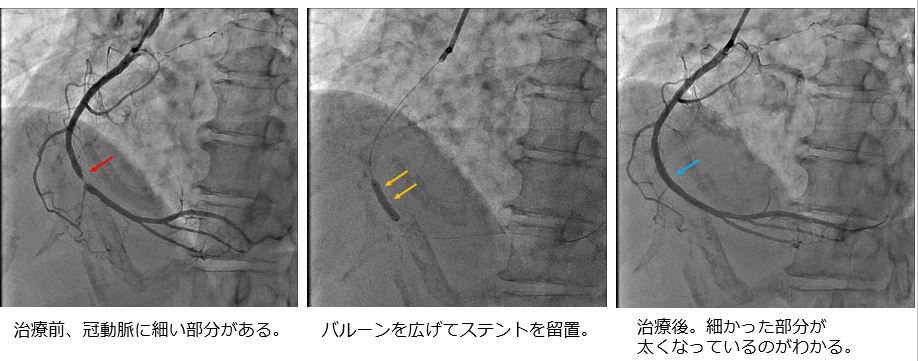

冠動脈カテーテル治療(PCI)は、手首や足の付け根の血管から細い管(カテーテル)を挿入し、狭くなったり詰まったりした心臓の血管を、バルーンやステントを用いて内側から広げる治療法です。胸を切らずに行えるため、体への負担が比較的少ないことが特徴です。